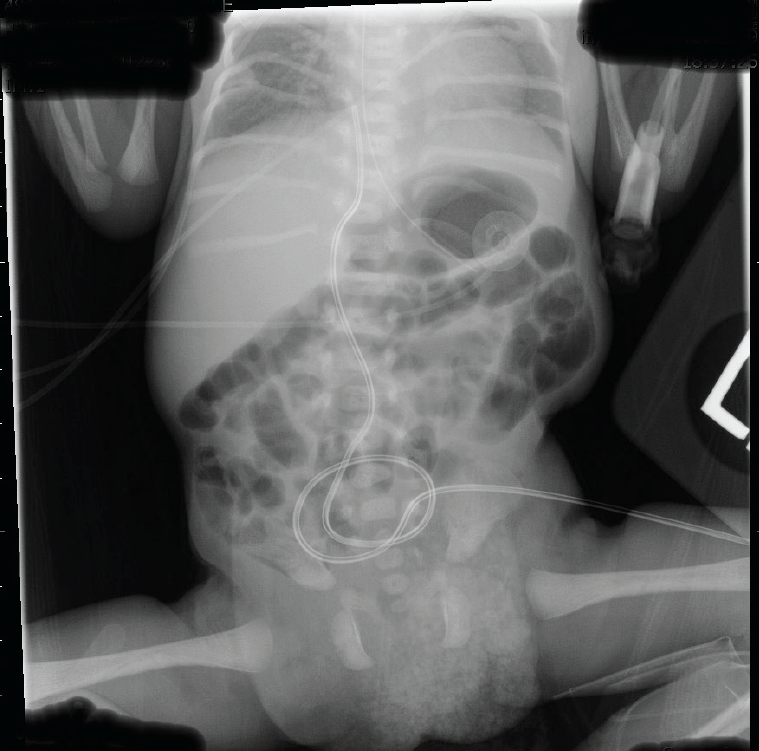

Plain chest and abdominal radiographs showed air-filled loops of bowel within the left lumbar region, scoliosis, and vertebral and costal abnormalities (Figure 2). The 6th through 12th ribs on the right and the 3rd through 9th ribs on the left were hypoplastic, and 1 rib was missing on the right. Thoracic vertebral bodies 8 through 10 also were hypoplastic, and mild lumbar scoliosis was noted.

Figure 2. Radiographs of the newborn showed costovertebral abnormalities, scoliosis, and a hernial sac with an air-filled loop.